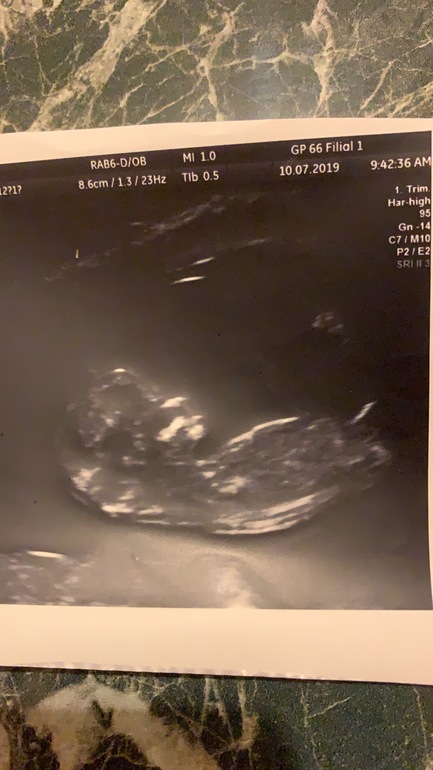

Вопрос про половой бугорок. УЗИ 12 недель. Что скажете?

Я так понимаю, беленькое пятнышко между ножек - это тот самый половой бугорок? Можно по нему сейчас что либо заподозрить?

Здравствуйте. Как думаете мальчик или девочка? фото 9 недель., 13 почт

И 13 недель то есть. В первый раз сказали мальчик

Во второй девочка))